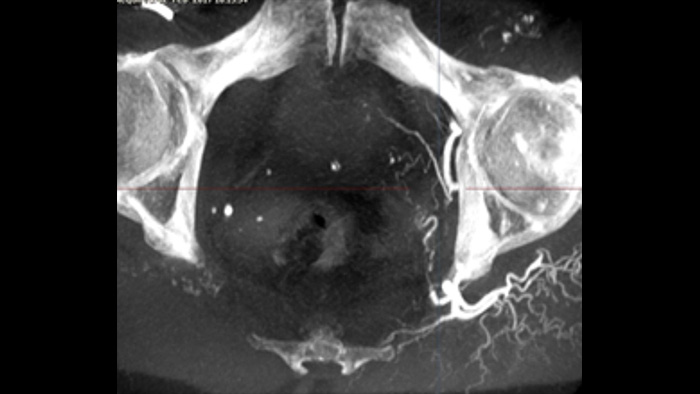

SmartCT Soft Tissue offers a cone-beam CT (CBCT) acquisition technique augmented with step-by-step guidance. Advanced 3D visualization and measurement tools are all accessible on the touch screen module at table side. You are guided through key steps to support you in acquiring CBCT images first-time-right1 and to streamline your workflow.